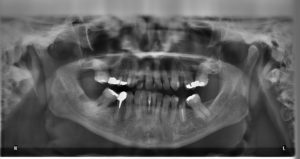

TAC Dental

¿Qué es un TAC dental? Un TAC dental es lo mismo prácticamente, pero con nombres diferentes, que una radiografía dental. No deja de ser una máquina especial de Rayos X pero, en este caso, para nuestra boca. Con esta máquina lo que conseguimos es lograr imágenes de gran nitidez de